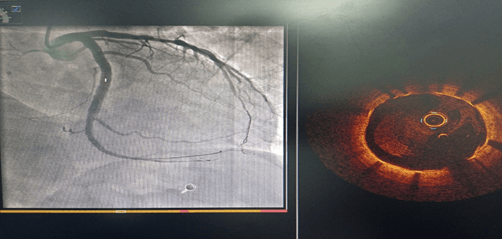

術(shù)前CAG示:左主干閉塞 IABP支持下開通閉塞血管

術(shù)前IVUS示最小管腔面積2.00mm2;術(shù)后IVUS示最小支架面積7.61mm2